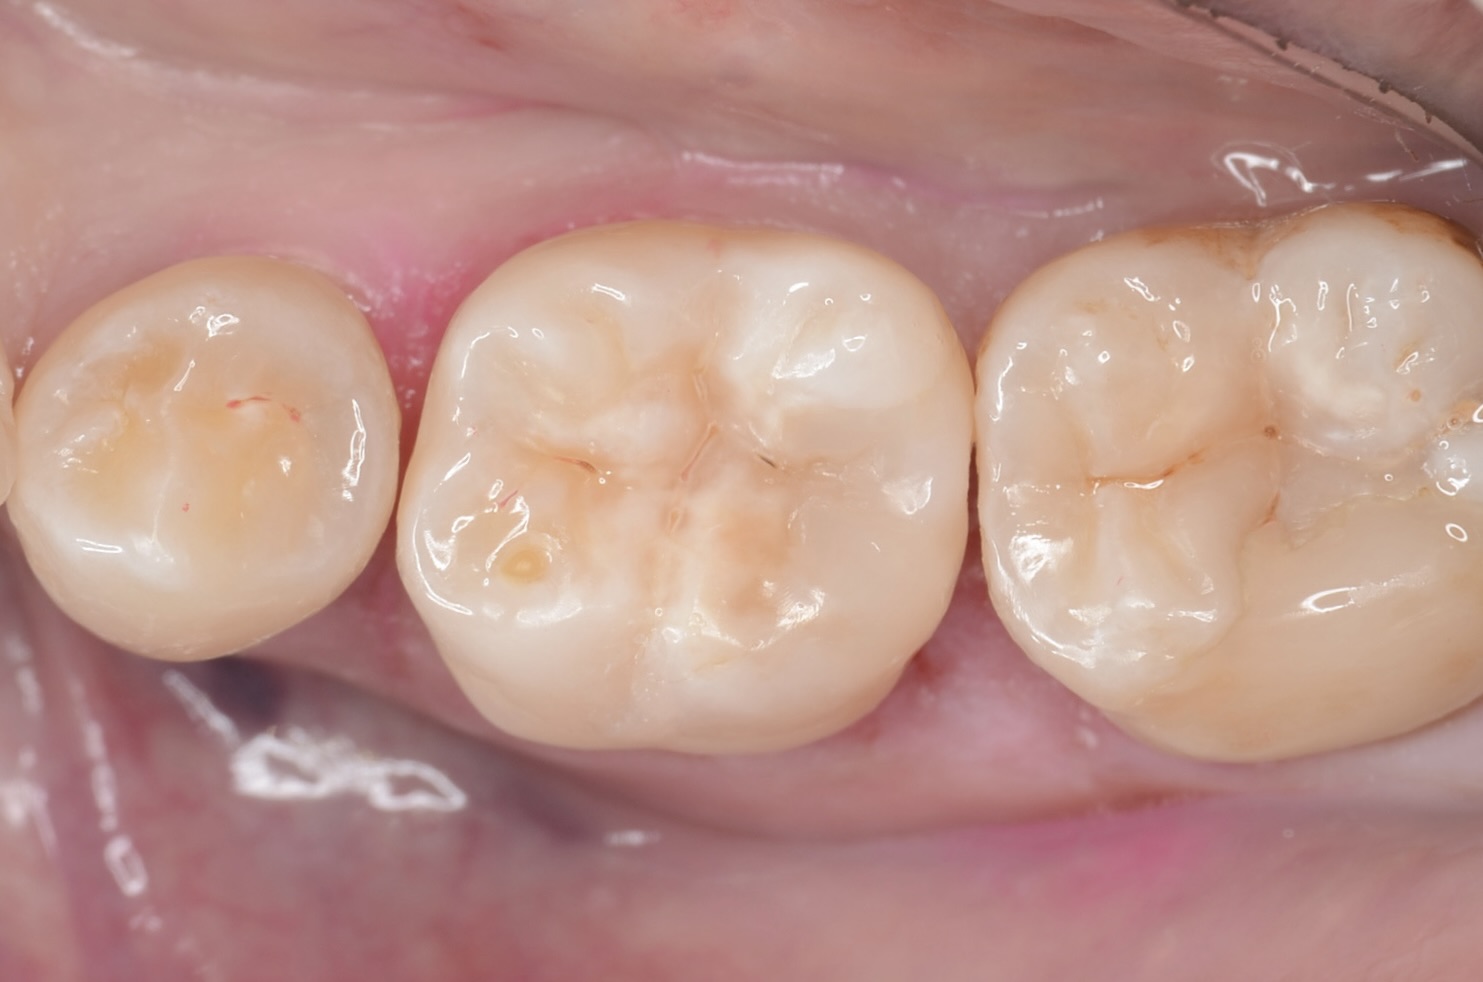

ダイレクトボンディング終了

ラバーダム撤去

歯と歯の間い隙間がありますが、すぐに閉じてきます。また5番と7番は次回以降治療します。 -

頬側面から見る

滑らかな段差の無い形態で形態に治す事ができました。